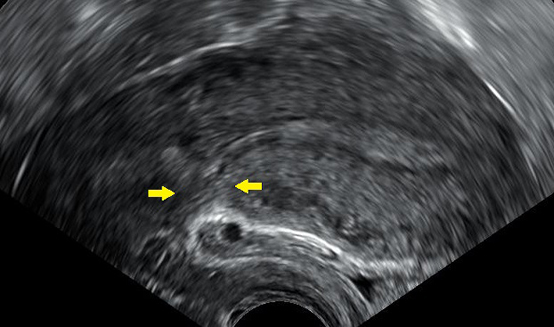

![]() |

제왕절개 수술을 받은 뒤 산모의 복부 초음파 사진. 수술 자국이 남아 있다. 제왕절개나 무통주사 등 의학적 간섭 없이 출산을 할 수 있다면 그 같은 방식이 산모나 태아에게 더 좋다는 게 대체적인 견해이다. (제공=해그스트롬 미카엘) |